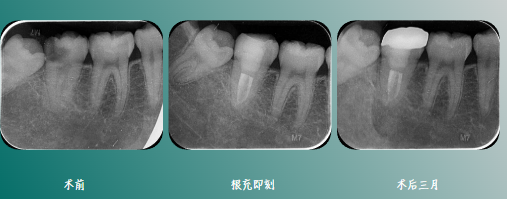

一周复诊,无不适,叩(-),牙体预备,全冠修复。

1、术前拍摄CBCT影像,观察根管形态,判断根管数目及走向,避免遗漏根管,再结合口内情况完善治疗。

2、术中使用显微镜,可清楚观察根管,为后续预备及封闭提供有效帮助,提高治疗成功率。

3、根管预备器械尽量选择小锥度,C形根管的舌侧壁较薄弱,避免带状穿孔,化学预备对C形根管至关重要,可选择声波类荡洗设备,柔软的工作头可进入不规则区域,降低器械分离的风险,也可选择一些特殊设备,如GenHeFile等。

4、对于C形根管,单尖法或侧方加压充填法无法对其进行有效的三维封闭,热牙胶充填是最好的选择,应选择耐高温类的糊剂,也应选择小直径的垂直加压器,以便将牙胶压入根管狭区内。